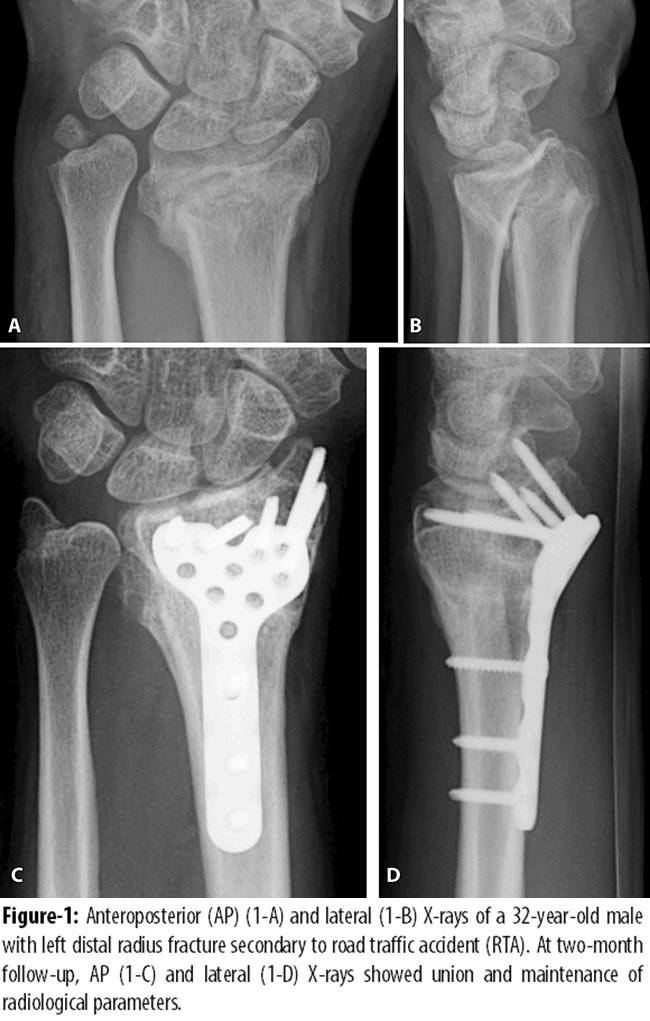

In our study, principle of angular stability was clinically applied by volar placement of locking plate for intra-articular distal radius fractures. Volar approach was preferred to facilitate reduction and plate fixation and to limit the risk of extensor tendon alteration. We evaluated the patients for the recovery of hand function and radiological parameters post fixation with LCP. Our results are consistent with earlier findings in terms of function of hand and radiological outcome.13-16 In most cases effective restoration of anatomic alignment was acquired and maintained (Table-2; Figures-1 and 2) regardless of the direction of fracture angulation.